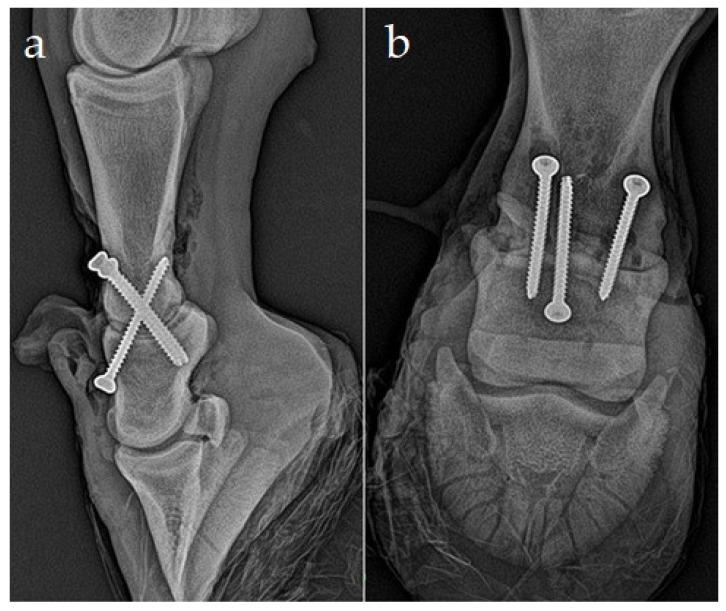

After the medial femoral condyle (MFC), the phalanges are the second most common site for osseous cyst-like lesions (OCLLs). Conservative treatment of phalangeal cysts on the convex surface of proximal phalanx presents a technical problem with access to the stoma of the cyst. Surgical therapy options usually aim to avoid cyst enlargement through drilling or screw placement or to encourage lesion filling with osteoconductive material. This paper describes a case of treatment of the OCLL in a yearling Czech warmblood filly with surgical arthrodesis, together with the packing of the OCLL with calcium phosphate biocement (CPB). The filly showed a chronic, moderate to severe, intermittent left hindlimb lameness. Dynamic examination combined with regional anesthesia and radiography confirmed a clinically significant large OCLL on the distal joint surface of the first phalanx. Treatment of the OCLL was performed by surgical arthrodesis of the proximal interphalangeal joint, using two paraxial and one axial crossed lag screw, after curetting of the cyst and filling with CPB.

除股骨内侧髁外,指骨是骨囊肿样病变(OCLLs)的第二大常见部位。近端指骨凸面指骨囊肿的保守治疗存在囊肿造口难以触及的技术问题。手术治疗方案通常旨在通过钻孔或螺钉置入避免囊肿增大,或促进病灶用骨传导材料填充。本文描述了一匹一岁捷克温血小母马的OCLL采用手术关节固定术治疗的病例,同时用磷酸钙生物骨水泥(CPB)填充OCLL。这匹小母马表现为慢性、中度至重度、间歇性左后肢跛行。动态检查结合区域麻醉和放射摄影证实,第一指骨远端关节面有一个临床上显著的大型OCLL。在刮除囊肿并用CPB填充后,采用两枚近轴和一枚轴向交叉拉力螺钉对近端指间关节进行手术关节固定术,治疗OCLL。